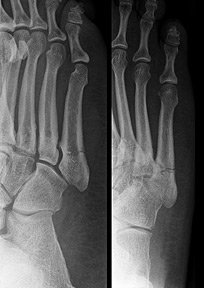

Avulsion fractures of the tuberosity are the most common fractures involving the proximal fifth metatarsal. Avulsion fractures occur proximal to the metaphyseal-diaphyseal junction. (Figure 2) If not displaced or comminuted, these fractures uniformly heal well with conservative treatment within three weeks.

It is important to differentiate avulsion fractures from an apophysis and from a fracture at the metaphyseal-diaphyseal region, as the treatment and healing time can be vastly different. The avulsion fracture is usually perpendicular to the long axis of the fifth metatarsal and the fracture is through the tuberosity and does not involve the metaphyseal-diaphyseal junction. In contrast to fractures, an apophysis has an oblique orientation and the lucent line between the metatarsal and apophysis should align parallel to the diaphysis. (Figure 3)

Fig. 2: Avulsion fracture. Note the oblique fracture line through the tuberosity.